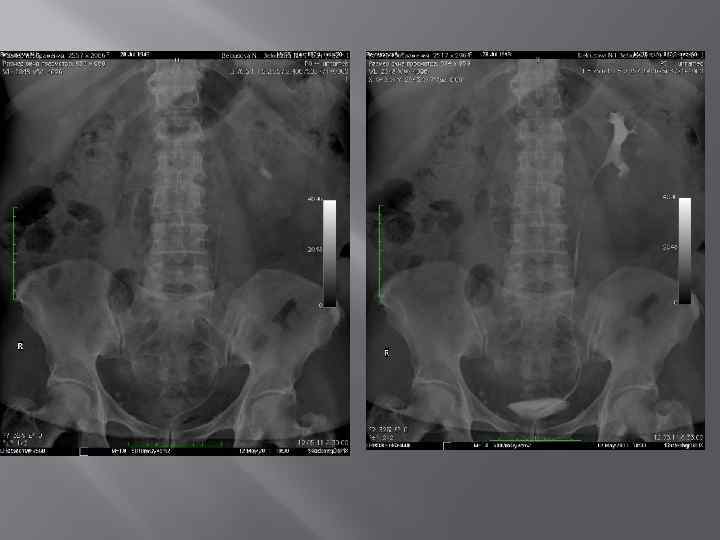

Камни в мочевом пузыре